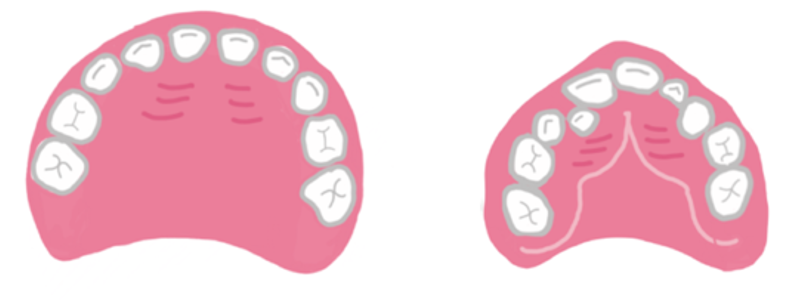

まるい顎と三角の顎、下の2つの顎のイラストを見比べてみてください。どちらが理想的な顎の状態でしょうか。

左側のまるい顎が理想的に育った顎です。歯と歯の間にスペースがありますね。一見、「すきっ歯」といわれるかもしれませんが、乳歯列ではこのスペース は本来あるべきです。でないと、乳歯より大きい永久歯が並んで生えてくることができませんよね。

一方、右側の三角形に近いかたちの顎は、少々問題を抱えて成長している顎です。歯と歯の間に隙間がなく、 お口の中にひずみが生じています。これは将来的に矯正治療が必要になる可能性を示すサインの一つ。赤ちゃんの頃からお口がポカンと開いていると、三角形の顎に育ちやすくなります。このような三角形の顎は、口呼吸が日常的になっている証。そして、これが「顎が小さい」の正体。

しっかりお口を閉じる習慣(鼻呼吸)ができていれば、理想的なまるい顎へと育っていきやすくなります。